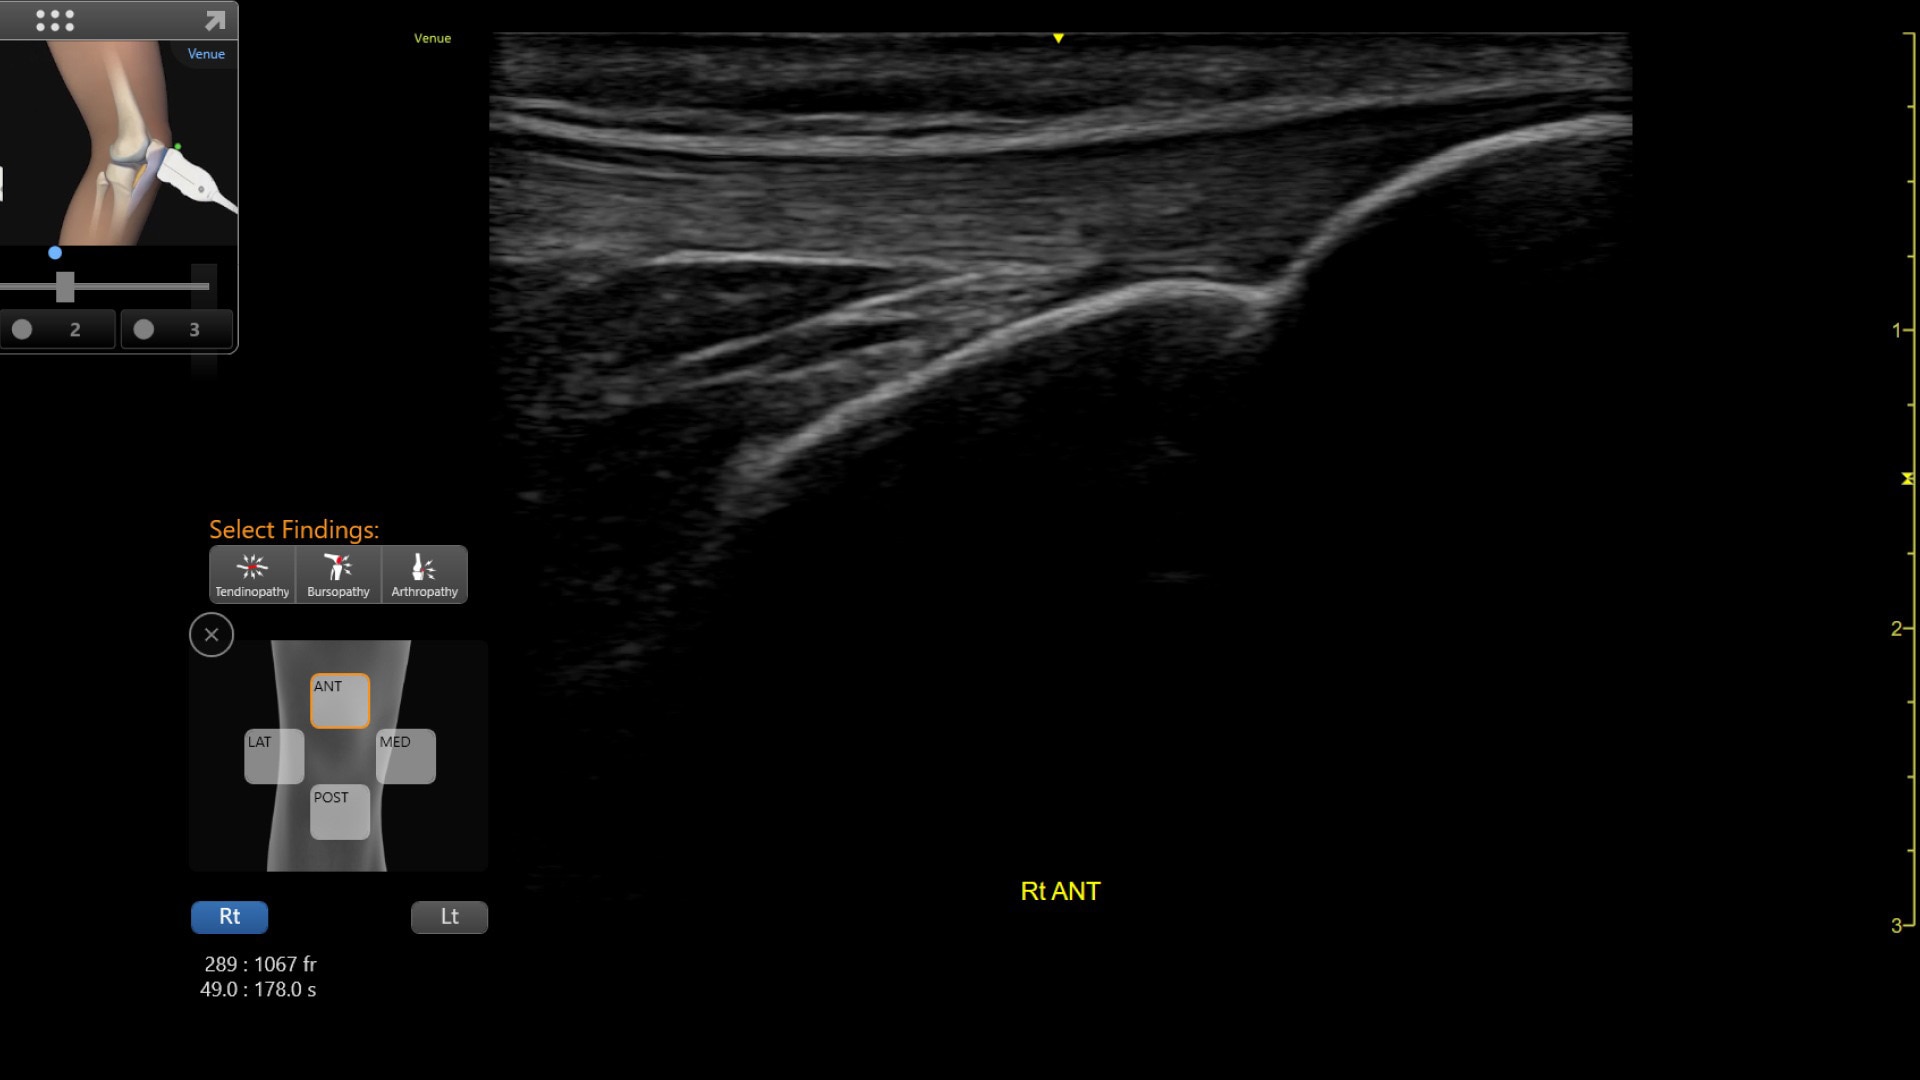

VENUE COACH MSK

Simplifying MSK scans

This easy-to-use exam documentation tool assists users through exams by providing reference images and anatomy markups. Multiple anatomical areas and helpful video tutorials help clinicians to acquire the scans they need.

• MSK Diagrams: Simplifies documentation and assists the clinician in follow up for patients. No need to manually type findings—you can simply assign a label from a pre-populated list that correlates with the images. Get a single view diagram with one click image storing, keep track of assessments and show trends in response to therapy.

• Reference Image: Reference image provides anatomy mark-ups to assist novice users in scanning the correct anatomy